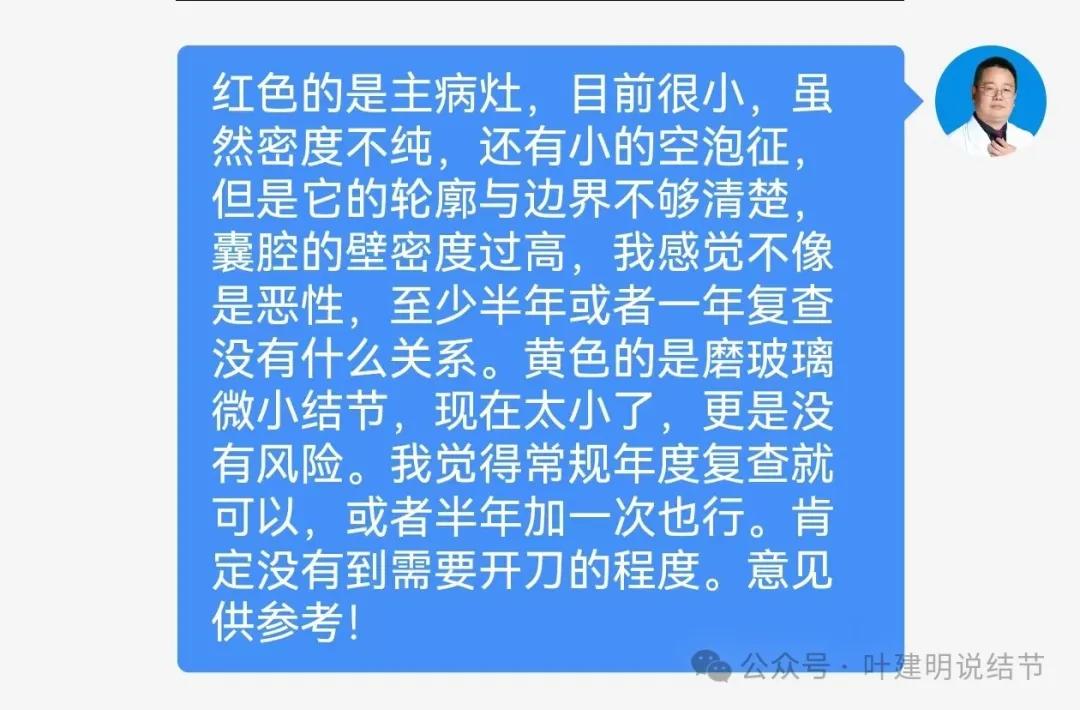

左上叶微小磨玻璃结节,轮廓较清,密度较淡,没有实性成分,考虑肺泡上皮增生或不典型增生可能性大,近期风险小,能随访。

右上叶混合密度结节,此灶周围有晕(很淡而边界欠清的磨玻璃),中间有小空泡征,空泡的壁又是实性密度的,空泡内壁圆而较光滑,邻近有小血管走过。

有血管经过病灶处,但距离这么近,血管却没有被影响或形成血管弯。绿色箭头处距病灶有一定距离,但也有淡而模糊的磨玻璃影。